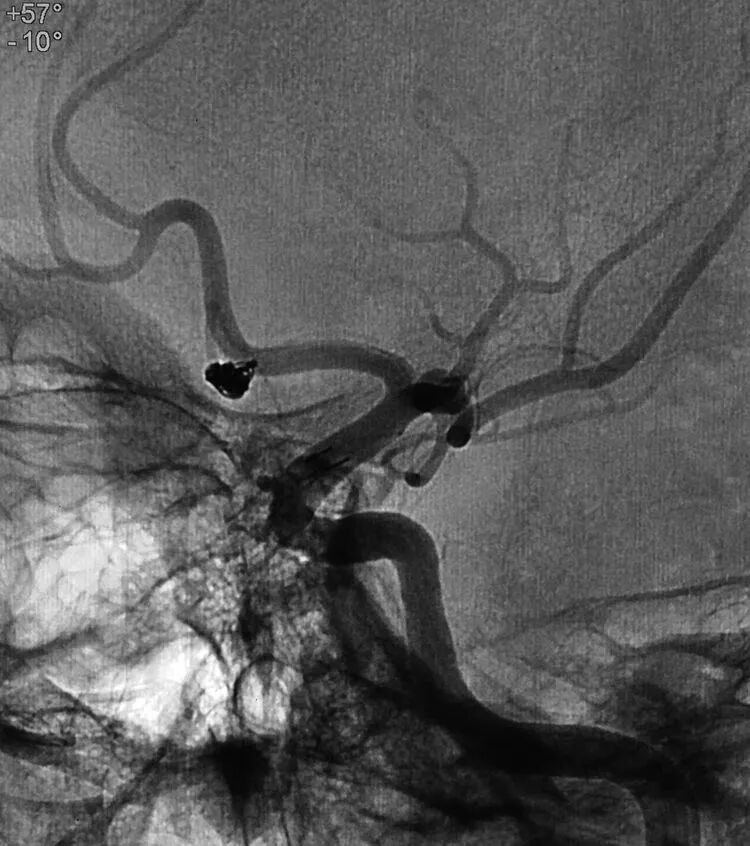

基底动脉顶端微小动脉瘤,是个有欺骗性的病例。从下面这个角度的造影看,瘤体长轴跟基底动脉主干平行,似乎用直头微导管栓塞即可

但从侧位造影和CTA观察,其实瘤体长轴还是跟基底动脉主干有成角的。这家医院的DSA机器没有三维重建工作站,只能参考CTA